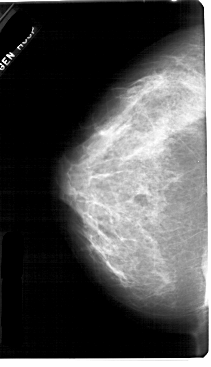

A_1752_1.RIGHT_CC

RIGHT_CC LINES 5491 PIXELS_PER_LINE 3001 BITS_PER_PIXEL 12 RESOLUTION 43.5 OVERLAY